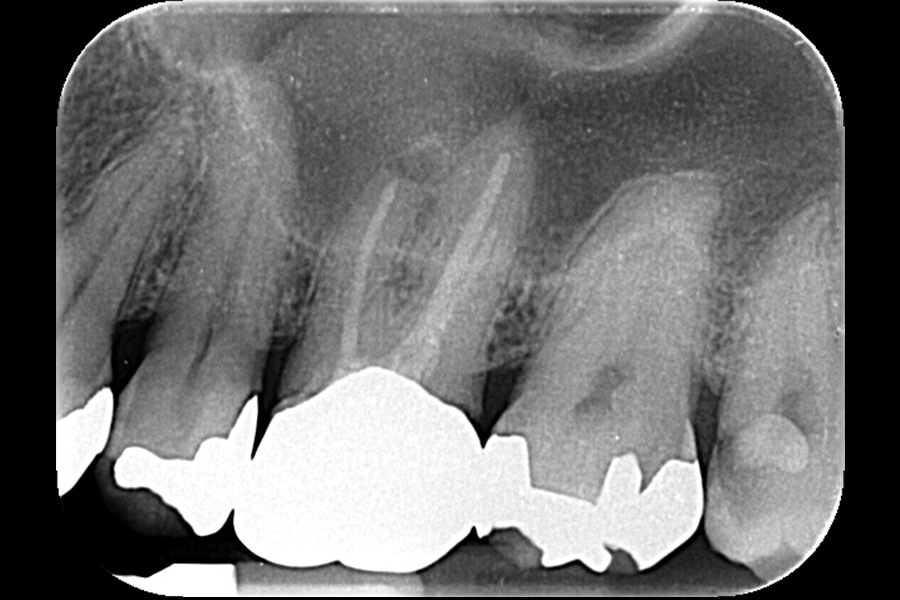

治療前